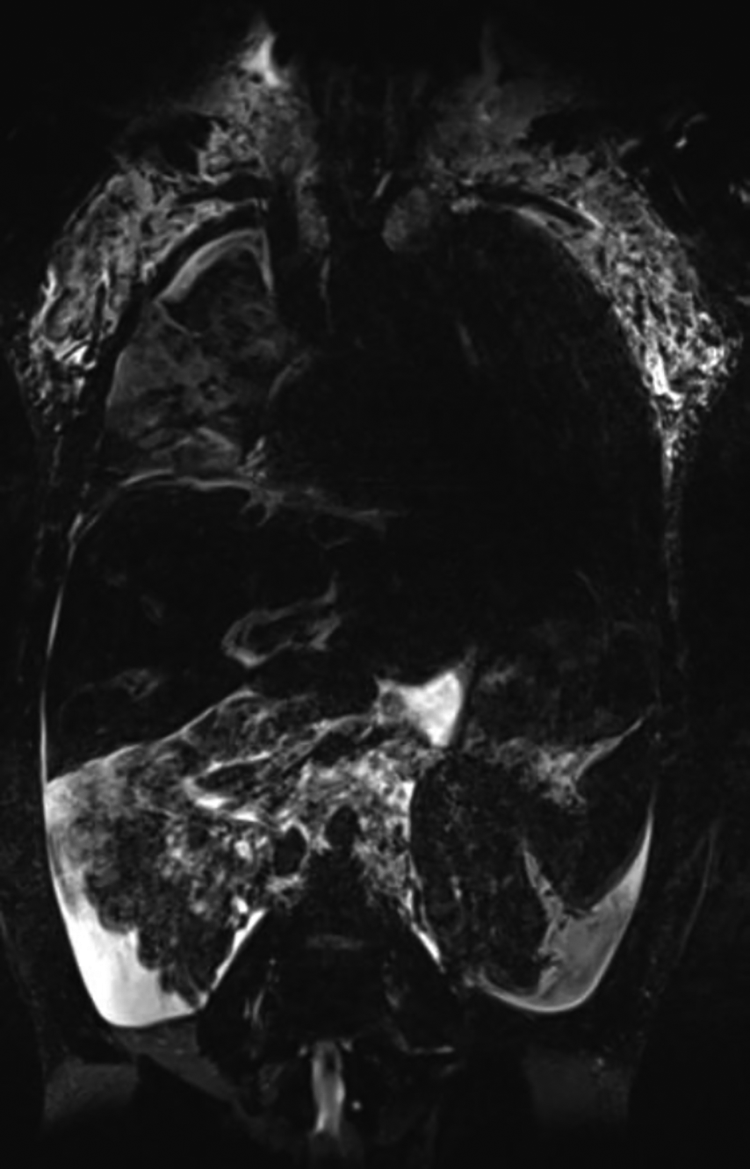

Non contrast heavily T2 weighted magnetic resonance lymphangiography imaging can easily be implemented during routine cardiac magnetic resonance imaging or as part of a thorough workup. It depicts areas of slow-moving non-bloody fluids resembling lymphatic tissue with high spatial resolution and serves as a screening tool for abnormal lymphatic distribution in the neck, the thorax and abdomen but lacks dynamic information. It can be done in any pediatric patient who is suitable for MRI.

Based on this imaging modality Biko et al. have published four types of lymphatic abnormality in patients after superior cavo pulmonary connection. In this study infants with higher degree of neck and thoracic lymphatic abnormalities were more likely to have failure of Fontan completion and a longer postoperative stay. Most notably a need for cardiac transplantation and death only occurred in infants with involvement of the lung parenchyma (type 4) (Figure 6). This imaging should therefore be used as a screening tool in all patients prior to Fontan completion to assess postoperative risk (48).

Figure 6

Native T2 weighted lymphangiography coronal projection depicting type 4 lymphatic abnormality with bilateral supraclavicular lymphatic abnormality and lymphatic networks extending into the lung parenchyma in a 13 year old patient.